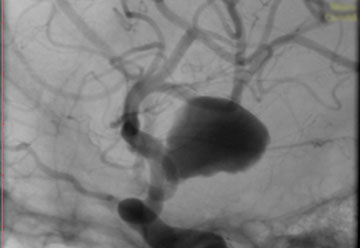

La paciente ingreso al Servicio de Hemodinamia el día martes 11 de febrero con un aneurisma cerebral gigante en la carótida izquierda y se le practicó una embolización; es decir una oclusión por dentro del mismo, donde se colocó un dispositivo denominado coils más un stent diversor de flujo. El procedimiento fue exitoso y contó con la colaboración de médicos neurointervencionistas del Instituto Oulton de la Ciudad de Córdoba.